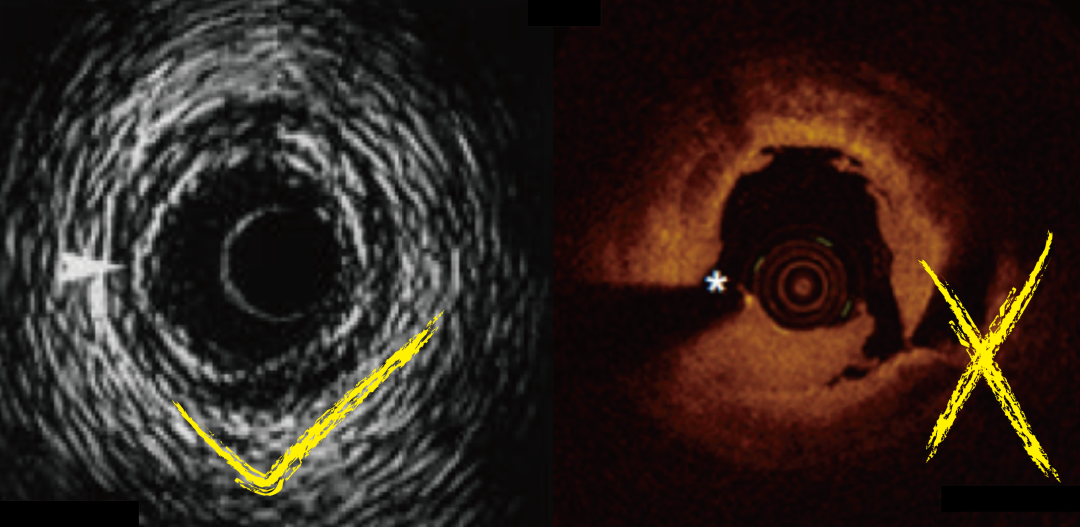

3.2.2 IVUS指导[推荐]

当术者无法将导丝推送到假腔时,最佳选择是使用IVUS指导进行导丝操作。术者应通过植入在假腔中的导丝推送IVUS导管,并识别假腔的起点。然后,术者应确认在假腔起点处残余真腔的位置。术者可以利用侧支方向、IVUS导管在近端真腔和指引导管内的位置以及导丝和IVUS导管的相对位置等信息,在透视下识别残余真腔的位置和方向。然后,术者就能在 IVUS指导下进行高效的导丝操作,以快速进入真腔。尽管OCT指导下的 PCI近年来有所增加,但在夹层情况下OCT是禁忌的。OCT成像需要冲洗清除血液,这会导致假腔扩大。即使OCT器械已经置于手术台上,在严重冠脉夹层时也应准备IVUS导管。